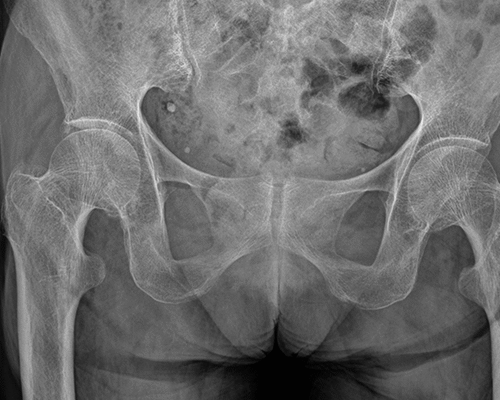

In this sheep model, after 13 months, the 29-mm screws (initial volume: 198 ± 1 mm 3 ) degraded by 41% (116 ± 6 mm 3 , mean difference 82 [95% CI 71 to 92]; p < 0.001), and after 25 months by 65% (69 ± 7 mm 3 , mean difference 130 [95% CI 117 to 142]; p < 0.001). After 13 months, the 24-mm screws (initial volume: 174 ± 0.2 mm 3 ) degraded by 51% (86 ± 21 mm 3 , mean difference 88 [95% CI 52 to 123]; p = 0.004), and after 25 months by 72% (49 ± 25 mm 3 , mean difference 125 [95% CI 83 to 167]; p = 0.003). After 13 months, the 16-mm screws (initial volume: 112 ± 5 mm 3 ) degraded by 57% (49 ± 8 mm 3 , mean difference 63 [95% CI 50 to 76]; p < 0.001), and after 25 months by 61% (45 ± 10 mm 3 , mean difference 67 [95% CI 52 to 82]; p < 0.001). Histologic evaluation qualitatively showed ongoing resorption with new bone formation closely connected to the resorbing screw without an inflammatory reaction. In patients treated with Mg-alloy screws after a mean of 2.5 years, the implants were radiographically not visible in 17 of 18 patients and the bone had homogenous texture in 15 of 18 patients. No clinical or patient-reported complications were observed.

In this sheep model, Mg-alloy (ZX00) screws showed a resorption to one-third of the original volume after 25 months, without eliciting adverse immunologic reactions, supporting biocompatibility during this period. Mg-alloy (ZX00) implants were not detectable on radiographs after a mean of 2.5 years, suggesting full resorption, but further studies are needed to assess environmental changes regarding bone quality at the implantation site after implant resorption.